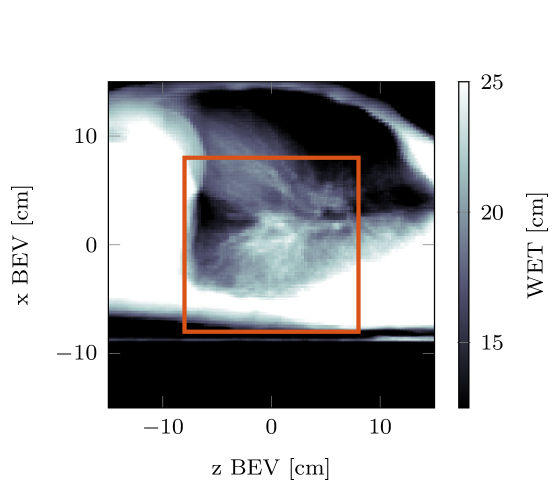

3.4 Helium radiographs with range shifter

In figure 10 two helium radiographs are compared, one acquired from the reference plan and the other acquired from a const RaShi plan. The energies of the helium radiographs where chosen so that both plans with and without range shifter, irradiate approximately the same crossecton of the tumor. The difference of both radiographs also indicates an increase in image noise when adding range shifters.

A disadvantage of using range shifters to optimize the residual helium range is that they introduce additional scattering, leading to beam broadening and an increased dose delivered to the patient. In addition to increased scattering, they lead to the production of more fragments. Furthermore, as illustrated in figure 10 the use of range shifters increases image noise in the simulated radiographs. Experimental investigation of the detection properties, especially when thick distal range shifters are used is necessary.